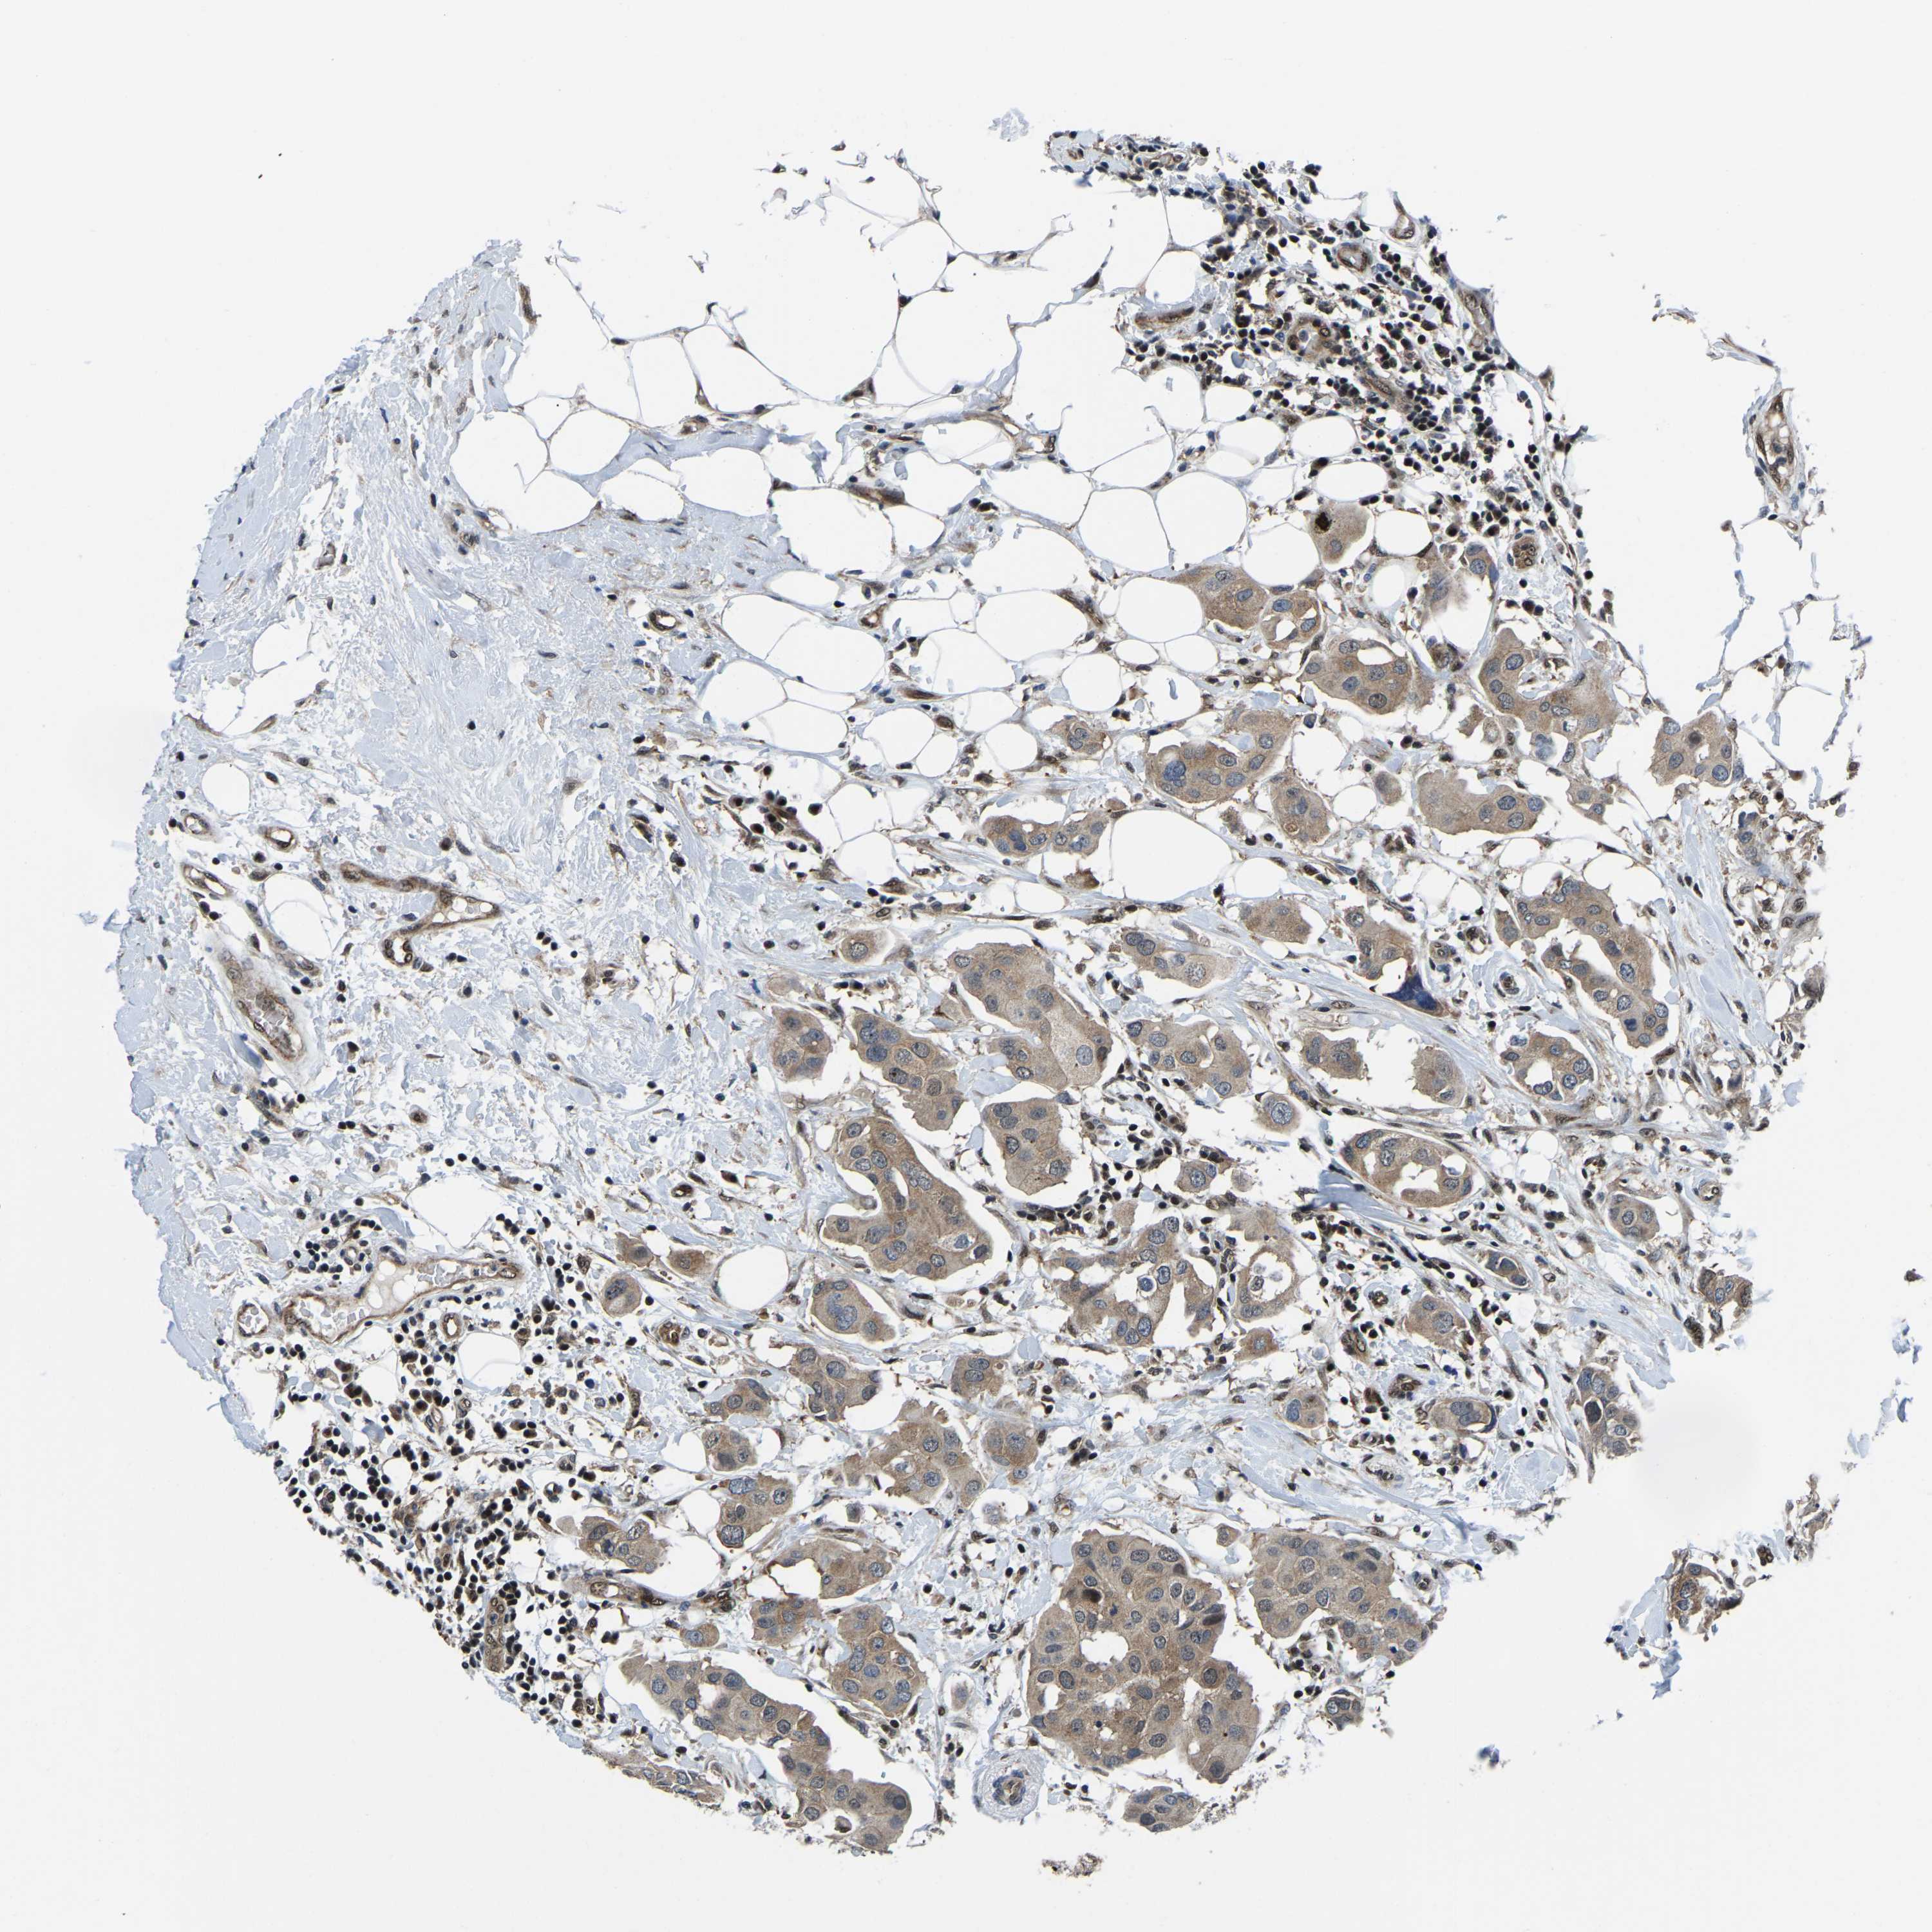

CANCER BREAST CANCER Show tissue menu

BRCA TCGA BRCA VALIDATION PROTEIN EXPRESSION